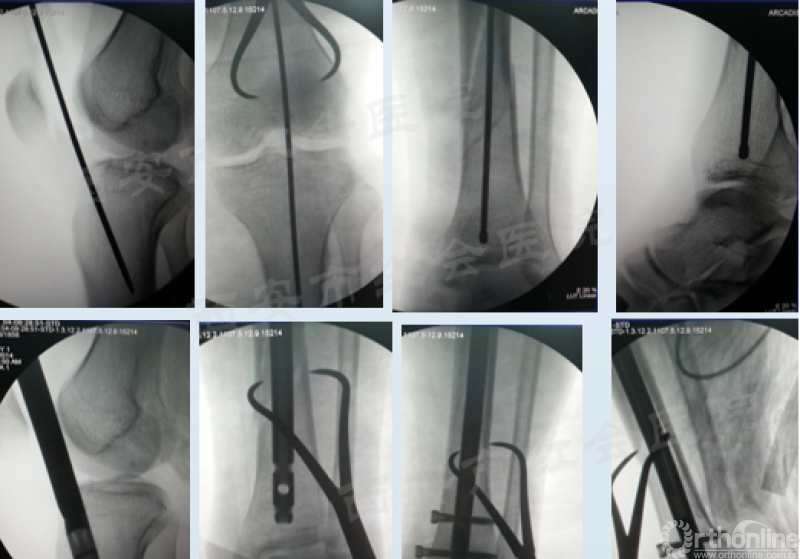

经典病例展示

(图片滑动展示)

髌外侧入路

仰卧于可透视手术床,铺巾前小腿下垫楔形垫。沿髌骨、髌腱外侧做一长约5cm的弧形切口,切开髌腱外侧支持带,牵开并保护脂肪热,触摸入点,克氏针定位,透视证实,用套筒将髌骨和髌腱往内侧推移,开口,置入导针,随后对骨折进行复位,再按照标准流程植入髓内钉。